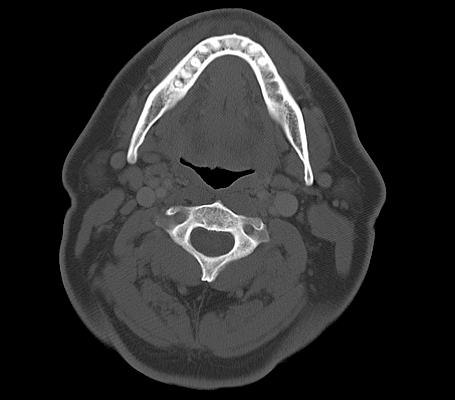

Alveolar Process

Angle of the Mandible

Body of the Mandible

Ramus of the Mandible